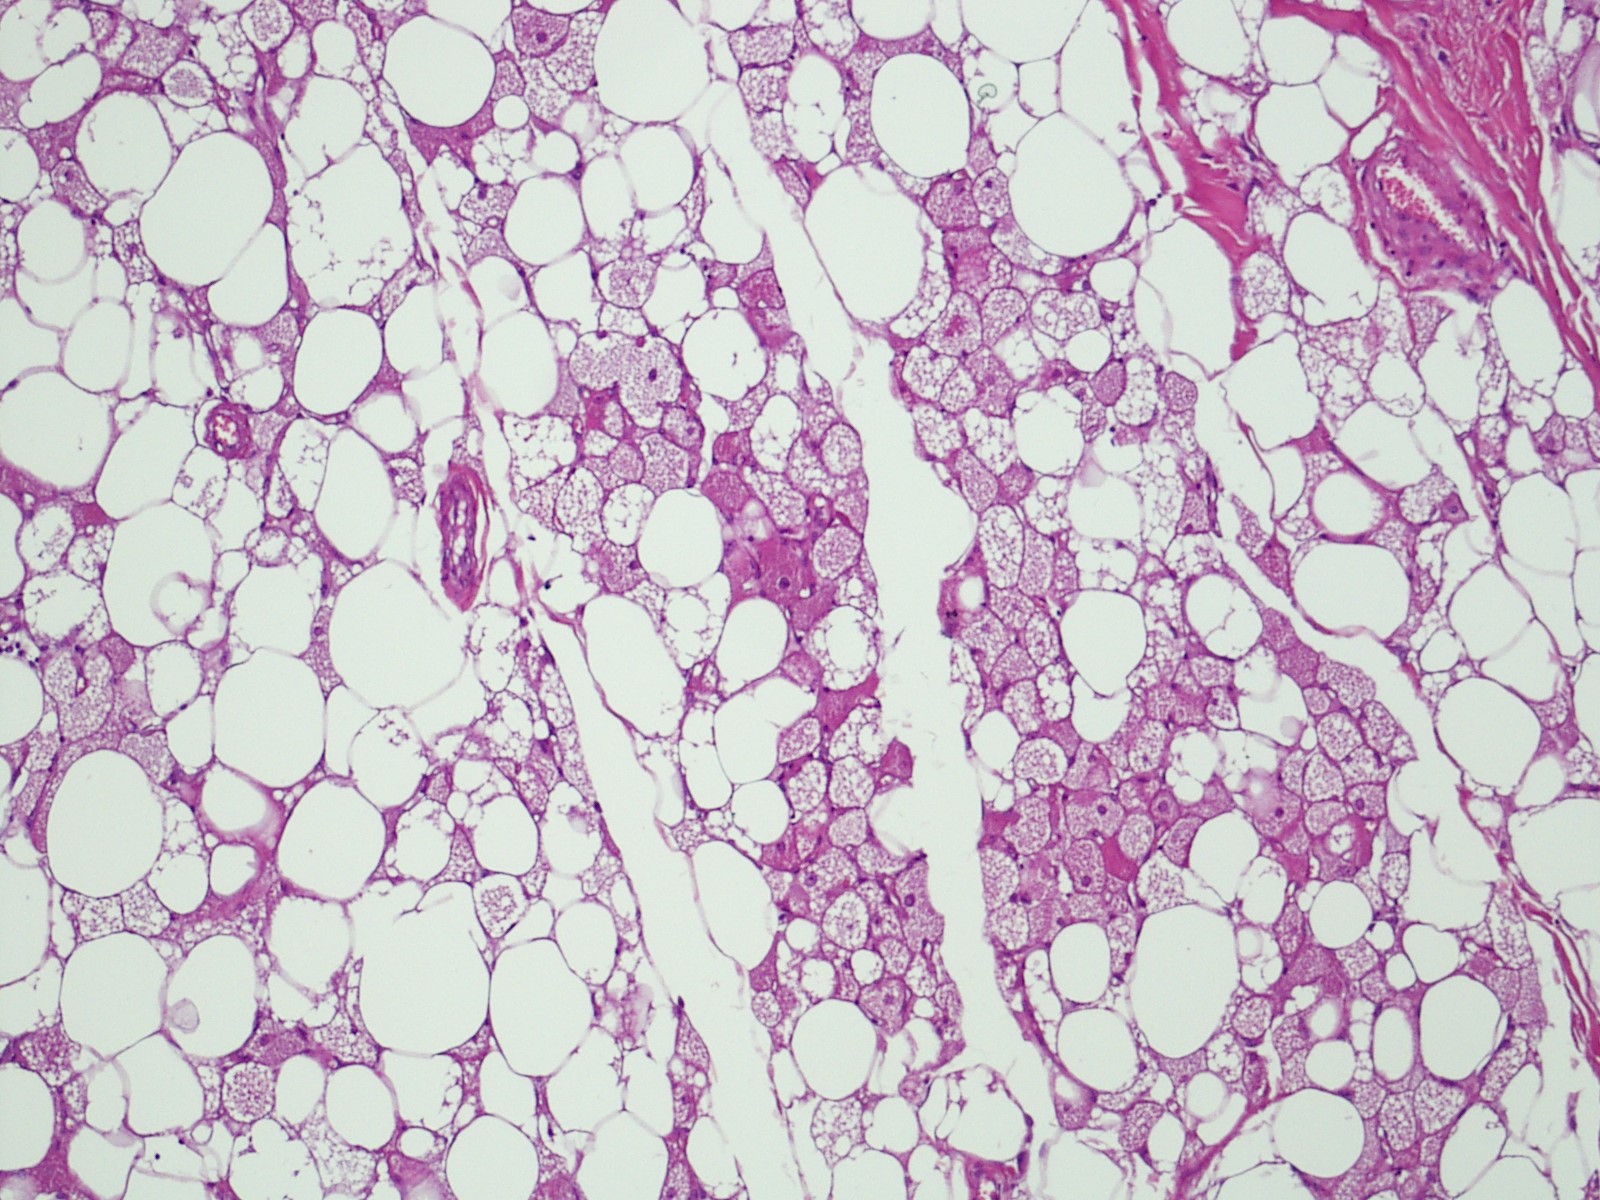

Microscopic (histologic) description

- Neoplastic lesion composed of polygonal brown fat cells with stromal cells in the background (Case Rep Oncol 2017;10:438)

- Large number of pale and eosinophilic brown fat cells with multivacuolated, eosinophilic granular cytoplasm and small central nucleus (about 70%) admixed with variable amount of univacuolated white cells (Case Rep Oncol 2017;10:438, Am J Case Rep 2020;21:e921447, J Comput Assist Tomogr 2019;43:793, J Pathol Transl Med 2017;51:499, Am J Surg Pathol 2018;42:951, Virchows Arch 2021;478:527)

- Multivacuolations resemble lipoblasts

- Morphological variations or subtypes: typical, myxoid (9%), lipoma-like (7%), spindle cell (2%), thick bundles of collagen fibers, presence of mast cells and exclusively containing brown fat cells (Case Rep Oncol 2017;10:438, Am J Case Rep 2020;21:e921447, Virchows Arch 2021;478:527)

- Cytological atypia, necrosis and mitosis is unusual (J Pathol Transl Med 2017;51:499, Am J Surg Pathol 2018;42:951, BMC Surg 2021;21:30)

Microscopic (histologic) images